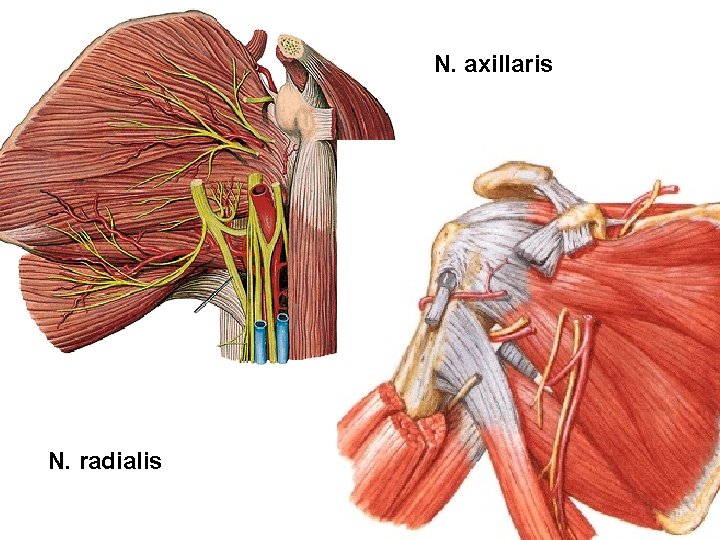

PARS INFRACLAVICULARIS (terminal branches) Fasciculus posterior - n. axillaris - n. radialis Fasciculus lateralis - n. musculocutaneus - radix lateralis n. mediani Fasciculus medialis - radix medialis n. mediani - n. ulnaris - n. cutaneus antebrachii med. - n. cutaneus brachii medialis

N. axillaris N. radialis

N. AXILLARIS (foramen humerotricipitale)

N. AXILLARIS - m. deltoideus - m. teres minor - art. humeri - n. cutaneus brachii lat. sup. A. circumflexa humeri post.

N. RADIALIS

N. RADIALIS sulcus n. radialis (a. profunda brachii)

N. RADIALIS - r. superficialis - r. profundus

N. RADIALIS - rr. musculares - m. triceps brachii - m. anconeus - m. brachioradialis - m. extensor carpi radialis longus - n. cutaneus brachii lat. inf. - n. cutaneus brachii post. - n. cutaneus antebrachii post.